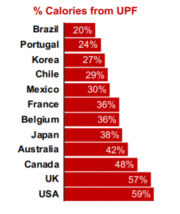

| 15:56, 25 בפברואר 2024 | צריכת UPF כאחוז מסך צריכת האנרגיה במדינות שונות בעולם, 2021.png (קובץ) |  |

153 קילו־בייטים | Roeitul | 1 | |